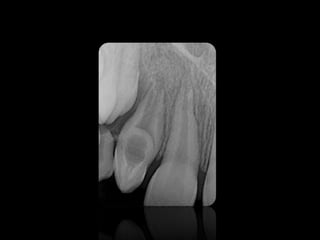

DENS IN DENTE